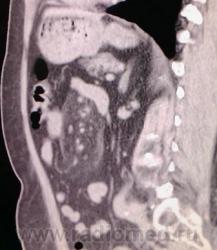

Прошу помочь КТ-специалистов. Медсестра 68 лет, частые боли в позвоночнике, непостоянные боли в животе. Направлена неврологом для исключения грыжи МПД поясничного отдела. Выявлены дегенеративные вараженные изменения позвоночника. По УЗИ норма, Hb=116 (начало 2009).На КТ: в брыжейке тощей кишки уплотнение жировой клетчатки (-45...-60ед.Н) размерами 12х5х7 см, окружает верхнебрыжеечную артерию, пронизано сосудами. Лимфоузлы брыжейки 0.5-1-1.5 см. Парааортальные л/у единичные, не увеличены.Контрастирования не проводилось - амбулаторное обращение. В понедельник давать заключение. Подозреваю ангиолипому. Буду рекомендовать обследование в стационаре.

Реконструкции

В вашем случае виден очень характерный для панникулита симптом ободка нормальной жировой плотности вокруг сосудов (симптом halo), ход сосудов не изменен, смещения или сдавления нет.